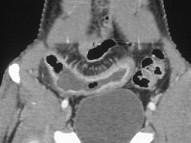

患者约30岁,结合图像,最可能的诊断为()

• A.缺血坏死性肠炎

• B.炎性腹泻

• C.克罗恩病

• D.腺癌

• E.溃疡性结肠炎